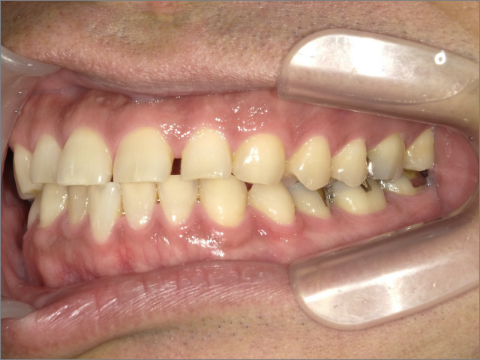

ご年齢 15歳女性 治療期間 2022/07/02〜2023/12/02(1年5ヶ月)

診断 110,000円(税込) アライナー 660,000円(税込) リテーナー 55,000円(税込)

ご年齢 15歳女性

治療期間 2022/07/02〜2023/12/02(1年5ヶ月)

診断 110,000円(税込)

アライナー 660,000円(税込)

リテーナー 55,000円(税込)

BEFORE

AFTER